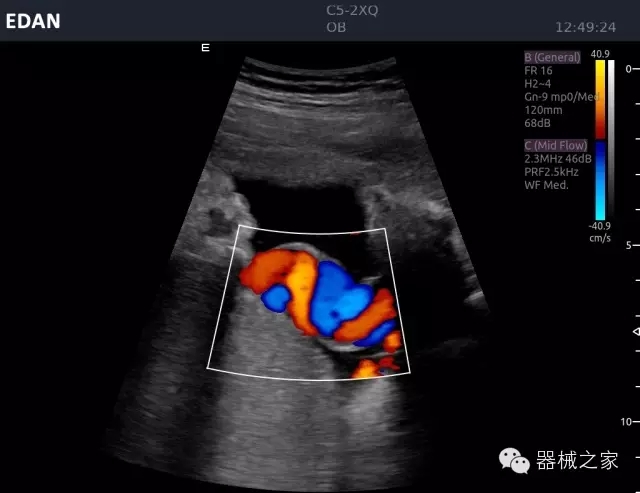

結(jié)甲

腎臟血流

肝血管瘤